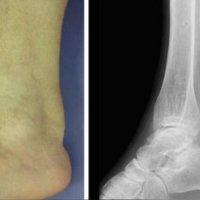

Achilles tendon xanthomas are painless soft tissue masses occurring most commonly at the distal one-third of the tendon and are usually bilateral and symmetrical.

In plain radiograph, this condition appearas as soft tissue densities in the Achilles tendon.